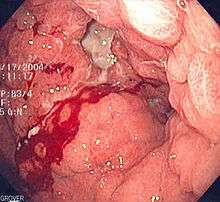

| Endoscopic image of linitis plastica, where the entire stomach is invaded with stomach cancer, leading to a leather bottle like appearance. | |

The appearance of the stomach is like a "leather bottle".[2] It is characterized by a thick, rigid stomach wall caused by diffuse infiltration of tumor cells and extensive fibrosis.